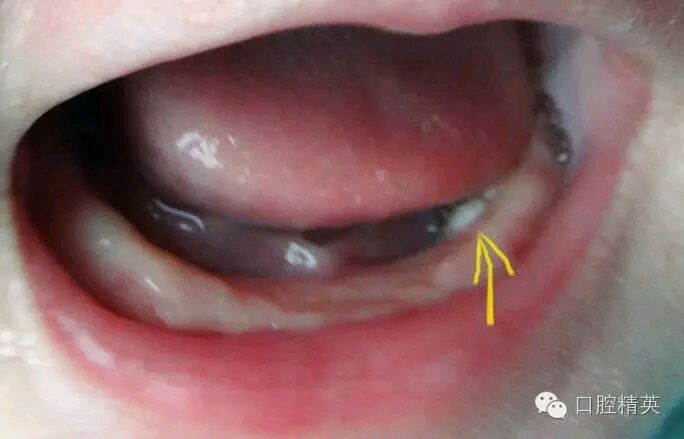

人们俗称的“马牙”常见于刚出生的新生儿或出生后1-2个月的婴儿,有的在口内牙床的牙龈边缘或上腭中缝两旁,是一种像小米或大米样大小的白色球状颗粒,少则数个,多则10余个不等,看上去很像一个个小牙齿,但“马牙”既不是真正的牙齿,也不是病态,而是胚胎发育过程中上皮细胞所形成的牙板。最初牙板和口腔上皮粘连,乳牙牙胚发育到一定的时候,牙板破碎。破碎的牙板一部分被吸收,没有被吸收的逐渐增生角化,在牙床上形成白色小球状颗粒的上皮珠,即“马牙”。

“马牙”一般无任何症状,对口腔颌面部的发育和健康也没有任何影响,无需任何处理。随着时间的进展,通过进食、吸吮的磨擦,“马牙”便可自行消失。